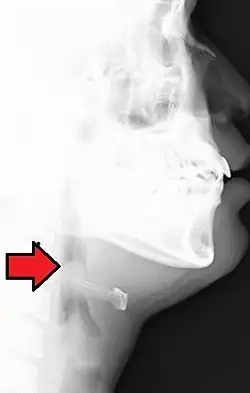

| Neck X-ray showing thumbprint sign | |

Epiglottitis was historically mostly caused by infection by H. influenzae type b (commonly referred to as "Hib").[1] Following the introduction of the Hib vaccine, pediatric cases of epiglottitis fell from 3.47 cases per 100,000 children in 1980 to 0.63 cases in 1990[8] such that it is now more often caused by other bacteria, most commonly Streptococcus pneumoniae, Streptococcus pyogenes, or Staphylococcus aureus.[1] Predisposing factors include burns and trauma to the area.[1] The most accurate way to make the diagnosis is to look directly at the epiglottis.[3] X-rays of the neck from the side may show a "thumbprint sign" but the lack of this sign does not mean the condition is absent.[1]

On lateral C-spine X-ray, the thumbprint sign describes a swollen, enlarged epiglottis.[11] A normal X-ray, however, does not exclude the diagnosis.[11] An ultrasound may be helpful if specific changes are present, but its use (as of 2018) is in the early stages of study.[11]